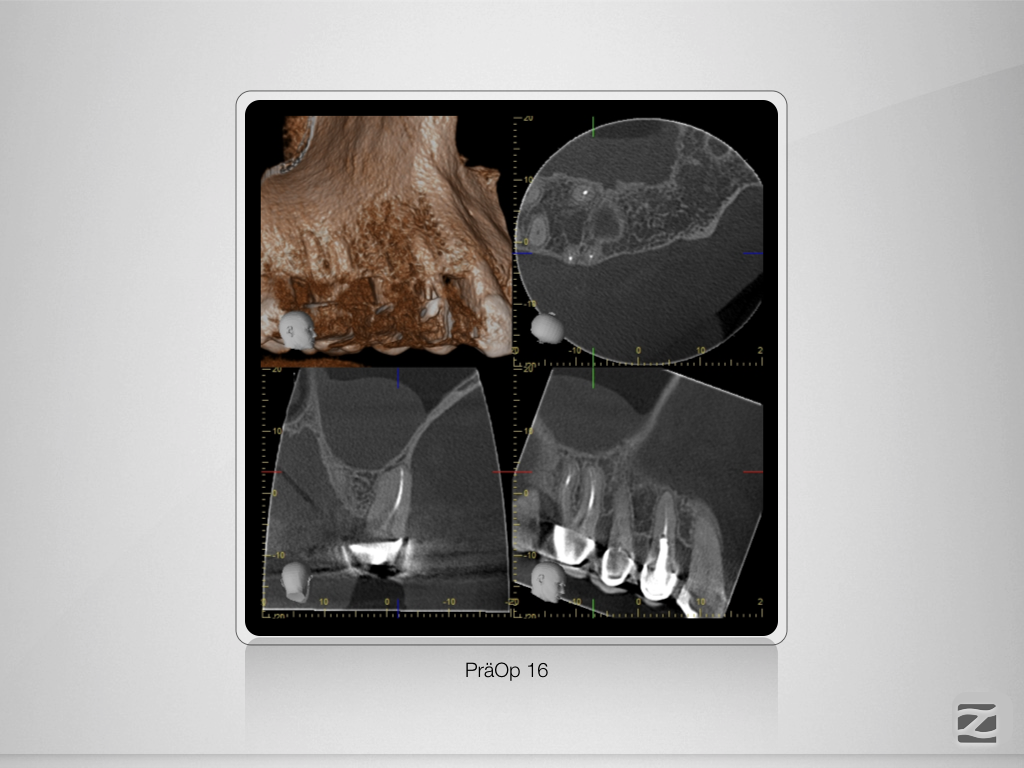

16-14D.002

Mein endodontischer Alltag